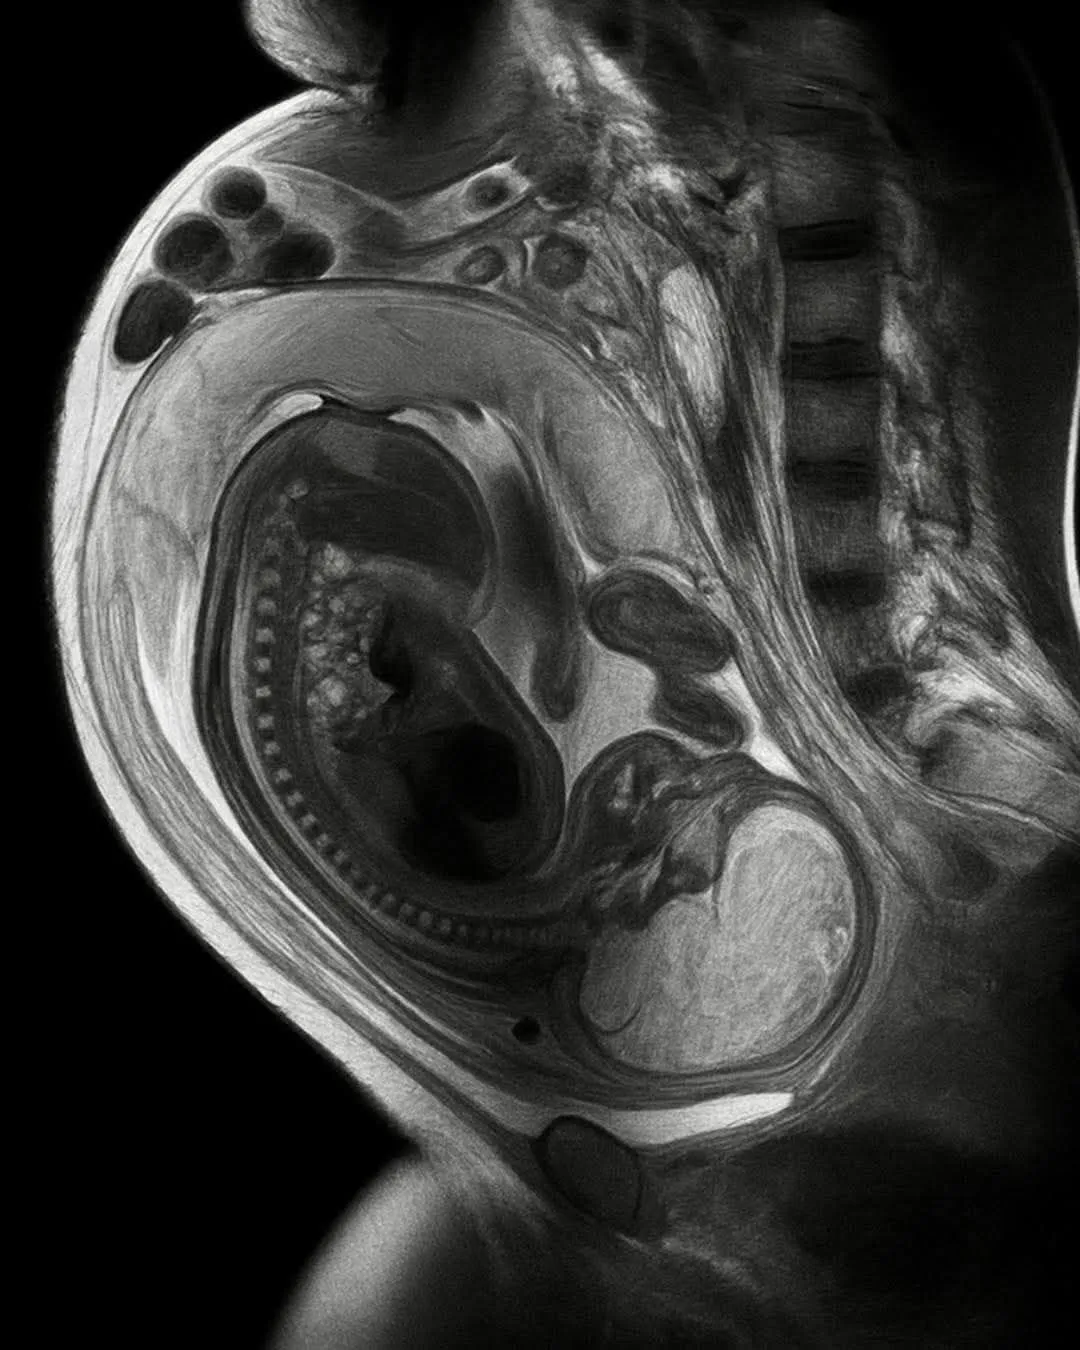

إذا أصيبت الحامل بتلف في عضلة القلب (مثل في حالة اعتلال عضلة القلب حول الولادة)، فإن خلايا جذعية من الجنين تنتقل إلى قلب الأم وتتحول إلى خلايا قلبية تساعد في الشفاء. ظاهرة طبيعية مذهلة تُسمى "microchimerism.

خلال فترة الحمل، تعبر خلايا الجنين المشيمة وتستقر في أعضاء الأم - القلب والكبد والرئتين والدماغ. إنها لا تمر مرور الكرام، بل تبقى. فحصت دراسة أجريت عام ٢٠١٢ أدمغة ٥٩ امرأة متوفاة من كبار السن، ووجدت خلايا الطفل موجودة في ٦٣٪ منهن، حتى بعد عقود من انتهاء الحمل. لكن التبادل متبادل. فخلايا الأم تنتقل أيضًا إلى الجنين، وقد تم رصدها في دماغ الطفل وأنسجته المناعية، واستمرت حتى مرحلة البلوغ. يُقدّر أن خلية واحدة من كل مليون خلية في جسمك الآن هي خلية أمك، وبالنظر إلى أن جسم الإنسان يحتوي على ما يقارب ٣٠ تريليون خلية، فهذا يعني ملايين من خلاياها تعيش داخلك.

عندما أُصيب قلب الأم في دراسات على الحيوانات، هاجرت خلايا جنين طفلها مباشرة إلى موضع الإصابة، وأصبحت نسيجًا قلبيًا للمساعدة في إصلاحه. لقد برمجت البيولوجيا نظام إصلاح في هذه العلاقة قبل أن يدرك أي منهما ماهية العلاقة.

هذه الخلايا الأمومية (غالباً خلايا جذعية أو خلايا مناعية) تستقر في أنسجة الطفل وأعضائه المختلفة (مثل الدم، الكبد، القلب، الرئتين، وحتى الدماغ)، وتبقى هناك لعقود طويلة، وقد تستمر مدى الحياة في كثير من الحالات.

وتعرف باسم الكيميرية الدقيقة الأمومية (Maternal Microchimerism).